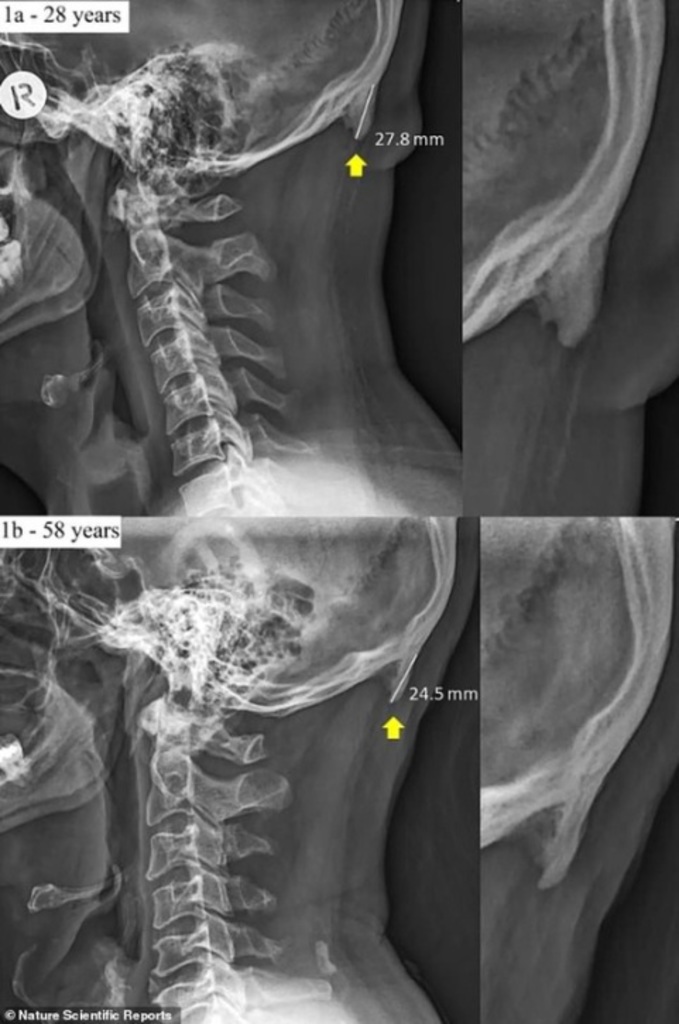

Nhiều người mọc gai nối dài ở sọ vì nghiện smartphone Các nhà nghiên cứu Úc đã phát hiện ra cấu trúc xương lạ lùng như chiếc gai bị nối dài thêm ở đáy sọ nhiều người thuộc type "ghiền smartphone". https://daklak24h.com.vn/doi-song/47065/nhieu-nguoi-moc-gai-noi-dai-o-so-vi-nghien-smartphone.html